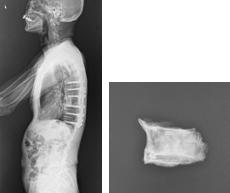

術前MRI T2像 術前MRI T1像 -

術後 X線 摘出された椎体